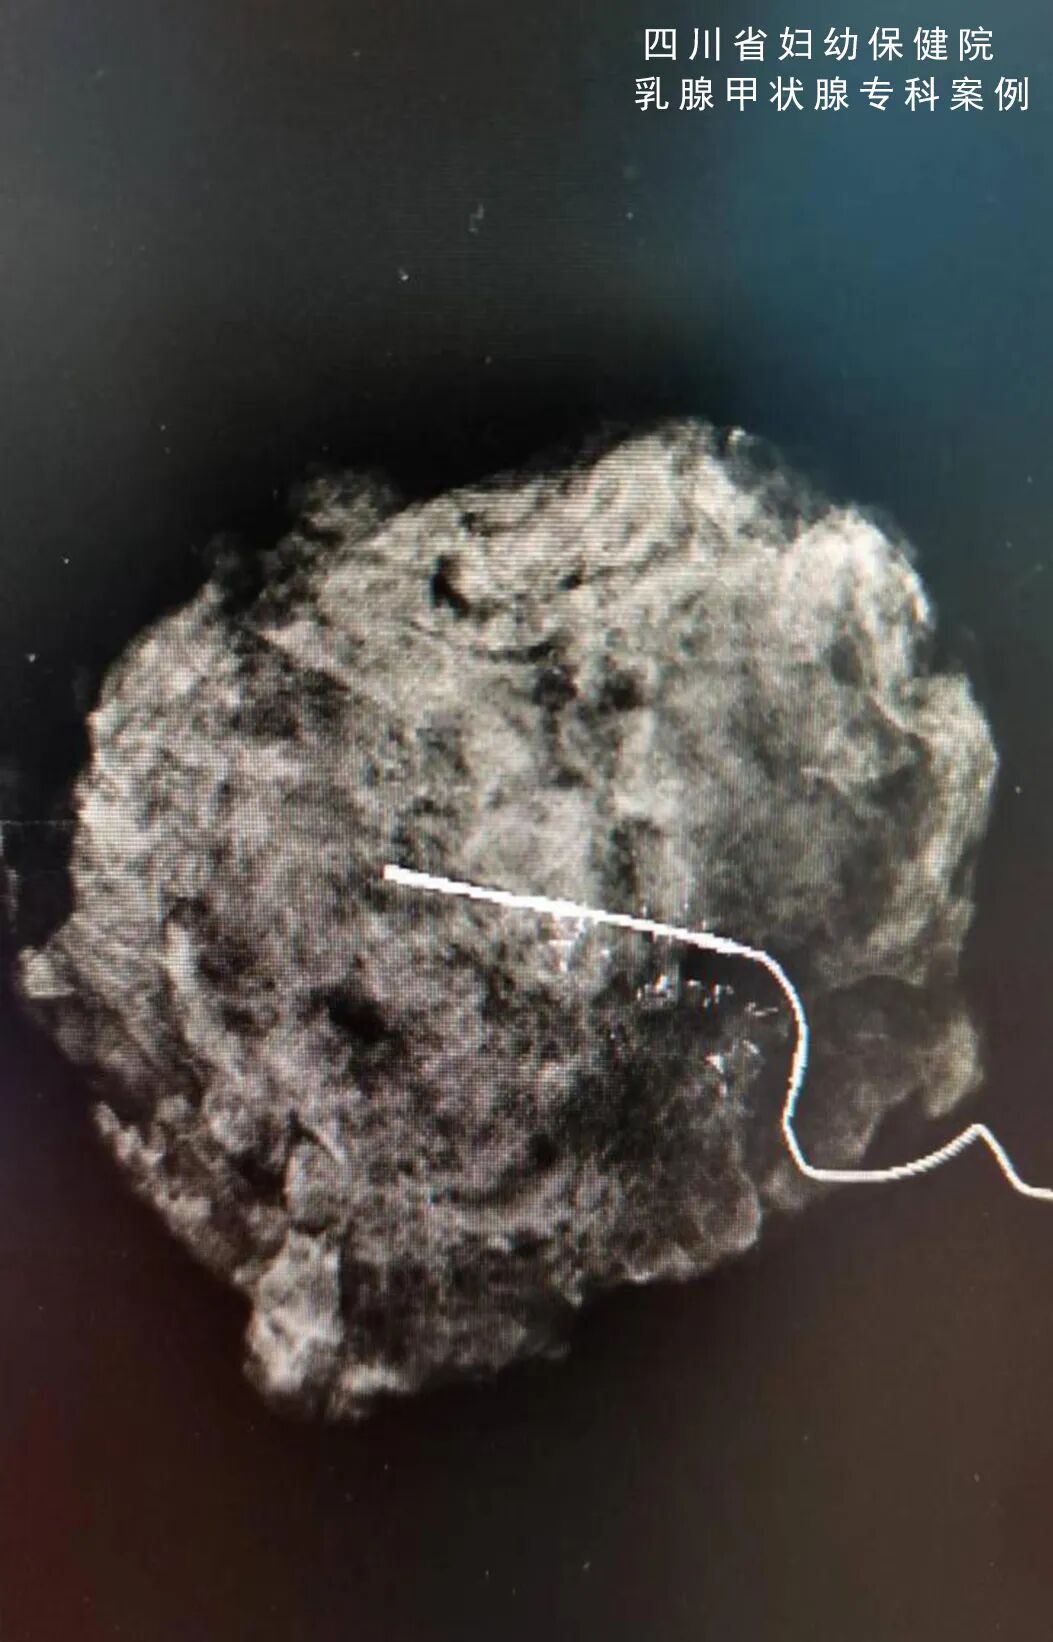

在这种技术的加持下,放射科医生通过给待活检的钙化灶在同一体位上±15°照片,计算机会自动计算钙化灶的三维坐标,医生只需要在局部麻醉后,将钩针或真空辅助旋切装置插入指定位置即可精确定位活检。

甚至通过断层影像技术,将乳腺分层显示,精确定位病灶所在的层次(深度),无需人工计算位置,且减少曝光次数,缩短操作时间,减轻病人痛苦。

(术中定位)